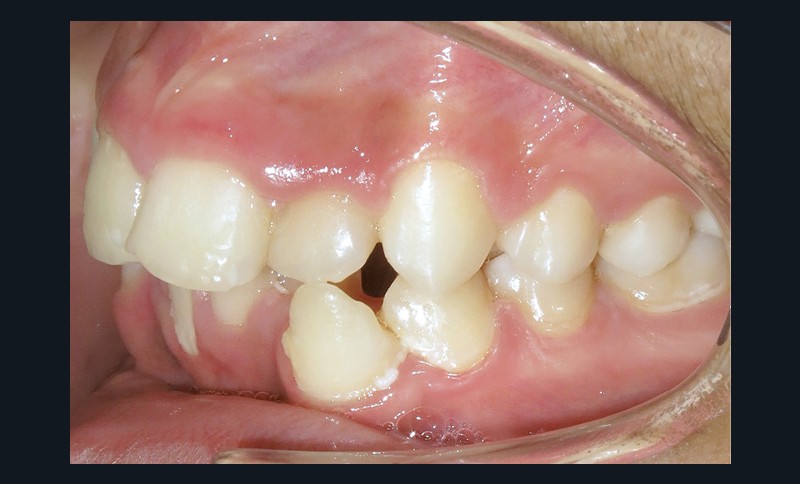

En denture adulte, la DDM est majeure avec un déficit de place estimé de 13 mm à la mandibule. Les lésions carieuses ont aussi touché les premières molaires permanentes maxillaires. La 26 a été avulsée et la 27 a pris sa place. Côté controlatéral, la 16 est fortement délabrée, rendant impossible sa conservation. Les molaires ayant plus mésialé à l’arcade mandibulaire, les rapports occlusaux sont de classe III. Les incisives sont versées vers l’avant, mais nous pouvons considérer qu‘il s’agit d’une biproalvéolie ethnique. Du point de vue squelettique, le patient présente une classe II squelettique par rétromandibulie sur un schéma facial hyperdivergent (fig. 1a-j).